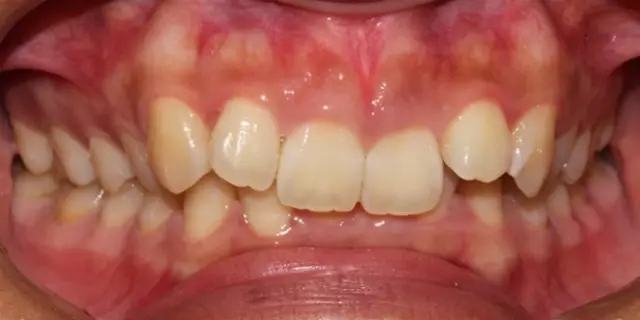

Damon 病例分享:安氏 II 類(lèi)二分類(lèi)露齦笑的矯治(董一磊)

患者信息

治療前后對(duì)比